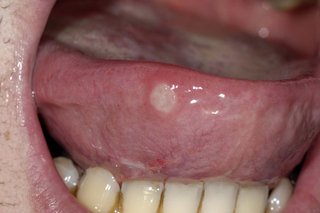

Mouth ulcer

A white, round ulcer on the underside of someone's tongue, which is poking out of their mouth.

Mouth ulcers are round, painful and swollen sores that look like blisters and can appear on the tongue, inside of the cheeks, or the lips.

Read about mouth ulcers.